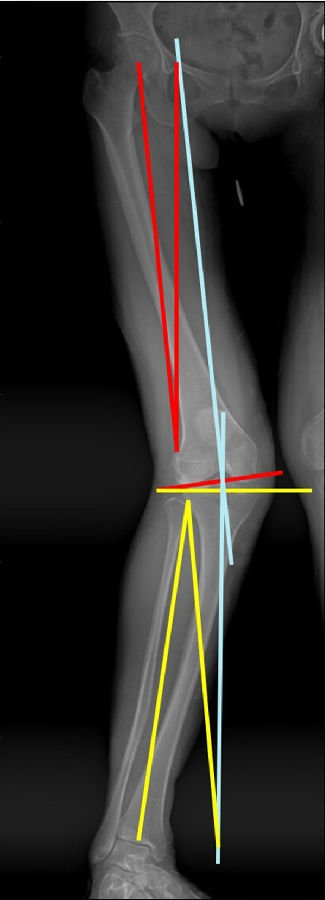

以两例病例展示术前设计的五步。患者一,女性,42岁,左膝疼痛2年,加重1年。

步骤一:判断内外翻畸形

画下肢机械轴,股骨头中心链接踝关节中心判断患者为内翻畸形还是外翻畸形。此患者为外翻畸形。

步骤二:判断畸形部位

量股骨远端外侧角和胫骨近端内侧角,判断畸形在股骨、胫骨还是关节内。此患者股骨侧有畸形,LDFA=76°,MPTA=81°,无关节内畸形。

步骤三:设定目标力线

以关节线为基准参考线,设定目标力线与关节线垂直。

步骤四:确定合页位置和截骨线方向

此患者计划股骨内侧闭合楔,胫骨内侧开放楔。

步骤五:Miniaci法测量角度

以股骨侧合页为旋转中心,以股骨头中心到合页的距离为半径,进行旋转,直到该线段与目标力线相重合,此时重合角度即为股骨需要闭合的角度,同时胫骨侧也能计算出开放的角度。此患者需要股骨闭合14°,胫骨开放8°。